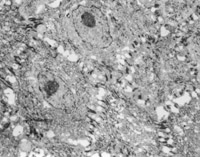

經(jīng)MEBT/MEBO治療5天,可見創(chuàng)面纖維細(xì)胞,成纖維細(xì)胞生長(zhǎng)比較活躍(圖5-3-13)。

5-3-13 MEBT/MEBO治療5天,成纖維細(xì)胞生長(zhǎng)活躍  TEM×2000